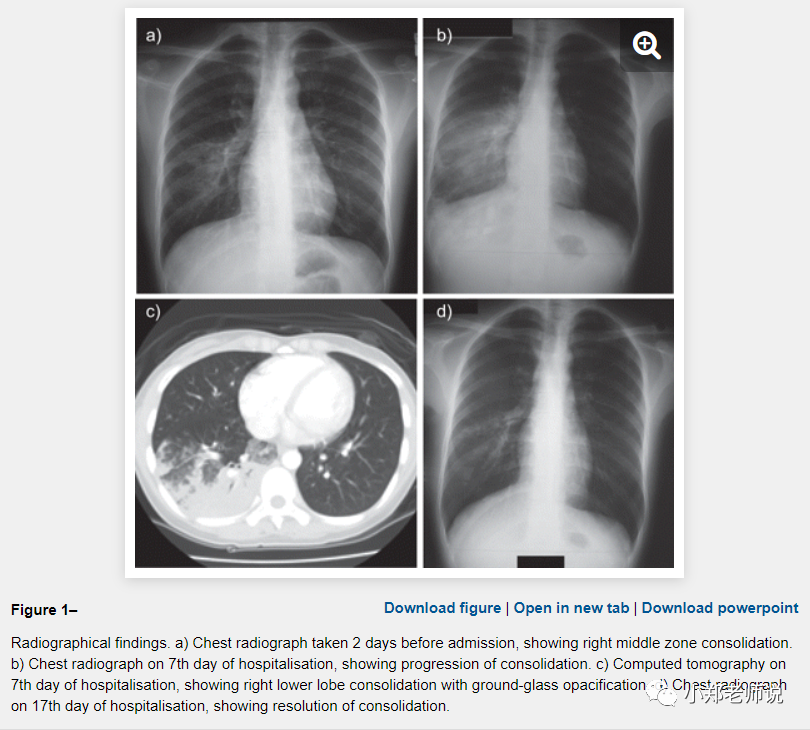

在极少数情况下,真正的症状严重,比如让我们看下面这位患者,注意她是 28 岁:

入院后,尽管给予了口服阿奇霉素,500 mg,每天一次,持续 9 天,但胸片显示持续发烧和肺部浸润进一步进展;

静脉注射头孢曲松,每日一次;哌拉西林-他唑巴坦,每 8 小时一次。

住院第 7 天进行了胸部对比计算机断层扫描,结果显示右下叶实变,伴有毛玻璃样混浊,右上叶后部有小而分散的毛玻璃样混浊。

由于持续发烧和肺炎,抗生素改为静脉注射替加环素(首次剂量 100 毫克,然后在住院第 10 天每 12 小时 50 毫克)。发烧迅速消退,肺部浸润得到改善。

患者于住院第19天出院。

—— 经过了足足 19 天住院,前后使用了四种抗生素,进行了反复多次不同的检查,终于才治愈。